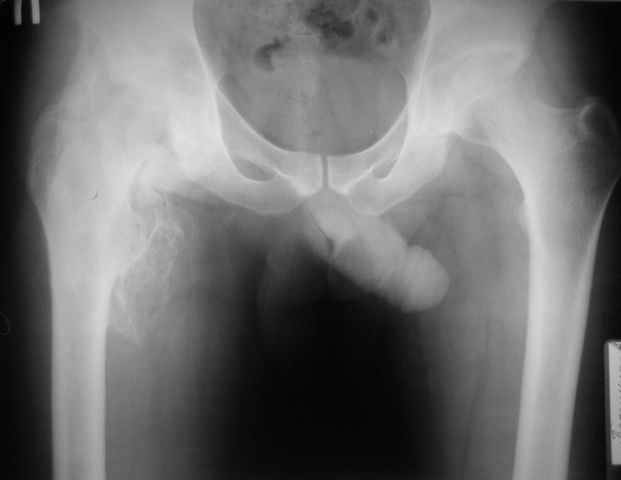

Около месяца на ИВЛ, В настоящее время неврологически компенсирован, ходит с ходунками, адекватен. Основная жалоба - отсутствие движений в тазробедренном суставе. Клинически наружная ротация 30 гр. умеренная мышечная атрофия, движения качательные. Рентгенологически-выраженные гетеротопические оссификаты в области правого тазобедренного сустава. Помогите определитсья с тактикой:Эндопротезирование? Сроки? Особенности. Заранее спасибо